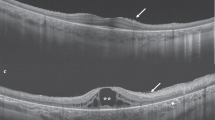

Multimodal imaging of the 16 cases with achromatopsia are provided in Figs 1, 2, and in the Supplementary Figure 1, and the main imaging features are summarized in Table 2. Complete multimodal imaging acquisition was obtained in the right eye for ten subjects, and in the left eye for six subjects. The eight control subjects selected for the semiquantitative NIR-AF and SW-AF plots did not differ from the 16 achromatopsia cases in terms of age (26.8 versus 25.1 years, P = 0.78) and gender (male:female ratio of 3:5 versus 5:11, P = 1.0).

Multimodal imaging in eight patients with achromatopsia showing the spectrum of abnormal near-infrared autofluorescence, and corresponding optical coherence tomography and short-wavelength autofluorescence images. Semiquantitative autofluorescence plots (right) show normalized autofluorescence signals, plotted after segmentation along semi-circles centered on the fovea. The horizontal dimension of the inner segment ellipsoid interruption on optical coherence tomography, if present, is reported as a striped area on autofluorescence plots. In Case #6, a hyperautofluorescent perifoveal ring was barely visible on short-wavelength autofluorescence (white arrowhead) but was clearly visible on the semiquantitative plot, illustrating the interest of this image process to emphasize details in low-quality, noisy images. SD-OCT = spectral domain optical coherence tomography; SW-AF = short-wavelength autofluorescence; NIR-AF = near-infrared autofluorescence; yo = year old; M = male; F = female.

According to the classification by Sundaram et al.14, horizontal SD-OCT scans through the fovea showed a continuous ISe in four patients, an ISe disruption in five patients, an absent ISe in three patients and an hyporeflective zone (HRZ) in four patients. A foveal hypoplasia, defined by the persistence of ≥1 retinal layer more internal than the outer nuclear layer at the fovea, was observed in eight patients. In all patients, the structural alteration on SD-OCT was graded similarly in both eyes.

On SW-AF, the most frequent abnormal feature was a pathognomonic perifoveal hyperautofluorescent ring, that was observed in n = 12 subjects (75%). The semiquantitative autofluorescence plots contributed to identify this ring in a low-quality autofluorescence acquisition due to photophobia, nystagmus and poor fixation (Case #6, Fig. 1). The four cases without perifoveal hyperautofluorescent ring on SW-AF had an abnormal foveal SW-AF profile, consisting in an enlarged (Case #5, Supplementary Figure 1) or a steep central SW-AF depression (Cases #1, Fig. 1; #2 and #12, Fig. 2).

On NIR-AF, the usual increased autofluorescence was present at the center of the macula in all eyes, with a variable signal strength ranging from very faint (Case #9, #11, Fig. 2) to intense (Case #13, #14, Fig. 1; and #8, Fig. 2). Within the macular hyperautofluorescent area, the most frequent abnormal feature of NIR-AF was a central hypoautofluorescent spot of variable size, that was observed in n = 7 subjects (44%), all displayed in Fig. 1. This central hypoautofluorescence, visible on the NIR-AF images, was confirmed by the semiquantitative NIR-AF plots, where it appeared as a central depression whose lowest value reached below the values of the control curve. Among those subjects, two presented in addition a perifoveal NIR-AF hyperautofluorescent ring, colocalizing with the border of the hypoautofluorescent area, as demonstrated by the sharp demarcation visible on semiquantitative autofluorescence plots (Cases #10 and #13, Fig. 1). The remaining cases that did not harbor a central hypoautofluorescent area on NIR-AF are displayed in Fig. 2 (normal appearance of the NIR-AF, n = 7) and in the Supplemental Figure 1 cases, #5 and #7, with borderline NIR-AF plots displaying an ill-defined central decrease in NIR-AF, that could not be clearly categorized into either group). Noticeably, a discrete foveal hyperautofluorescent spot was observed in n = 3 cases (Case #8, #11 and #15, Fig. 2) on the NIR-AF plots.

Characteristics of patients with foveal NIR-AF hypoautofluorescence and correlation to multimodal and clinical parameters

Patients presenting a central hypoautofluorescent area on NIR-AF were significantly older than those with normal NIR-AF (31.5 ± 9 versus 15.5 ± 6.6 years, P = 0.004). They also presented more frequently advanced outer retinal alterations on SD-OCT, with n = 5/7 cases presenting an absent ISe or an hyporeflective zone as compared to n = 1/7 cases among patients without foveal NIR-AF hypoautofluorescence (P = 0.051, near-significant difference). In addition, there was a strong, positive correlation between the size of the NIR-AF central hypoautofluorescent area, measured in degrees on the semiquantitative NIR-AF plots, and the size of the ISe defect, measured in degrees on horizontal SD-OCT scans (r = 0.67, P = 0.005). This correlation was stronger when restricting the analysis to eyes with central NIR-AF hypoautofluorescence and SD-OCT stage 2 or more (r = 0.93, P = 0.002). The size of the NIR-AF hypoautofluorescent area was also strongly correlated with the stage of structural damage on SD-OCT (r = 0.72, P = 0.002). Finally, patient age was also strongly correlated to the size of the hypoautofluorescent area on NIR-AF (r = 0.63, P = 0.009), and moderately to the stage of SD-OCT alterations (r = 0.52, P = 0.037), but not to the size of the hyperautofluorescent ring on SW-AF (P = 0.89). No relationship was found either between the size of NIR-AF hypoautofluorescence and the SW-AF hyperautofluorescent ring (P = 0.27). The diameter of this SW-AF ring was correlated to the size of the ISe defect on SD-OCT (r = 0.57, P = 0.021), but not the stage of SD-OCT alteration (P = 0.48). None of these imaging parameters was correlated to visual acuity levels. Similarly, no correlation was observed between genotype (CNGA3 or CNGB3 mutations) and phenotype on multimodal imaging (in term of SW-AF hyperautofluorescent ring, central NIR-AF defect, or SD-OCT grading). The case presenting a homozygous PDE6C mutation was not included in this analysis. In particular, although cases with CNGA3 mutations presented less frequently a perifoveal hyperautofluorescent ring on SW-AF than those with CNGB3 mutations (n = 5/8 (63%) vs n = 6/7 (86%), respectively), this discrepancy remained non-significant (P = 0.57). Multiple correlations are summarized in Table 4.